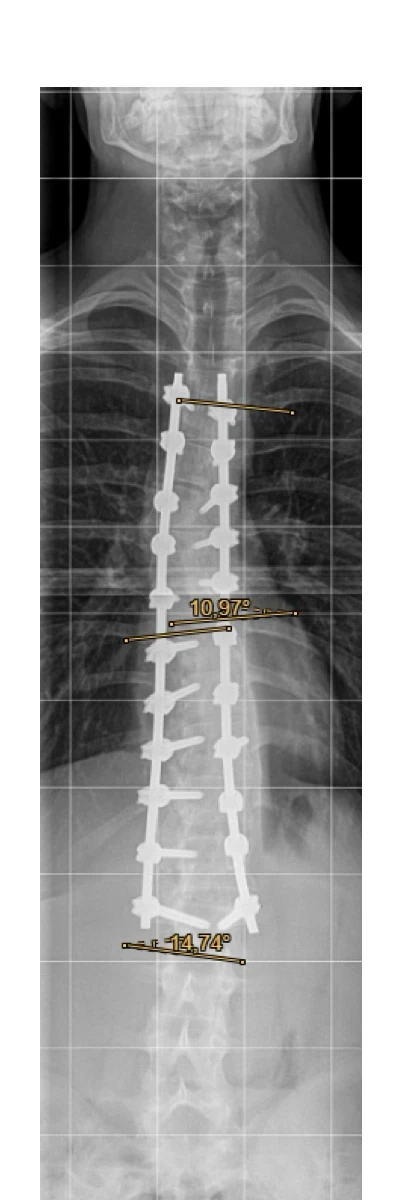

Post-OP Röntgenbild

mit Cobb-Winkel

Der Cobb-Winkel konnte insgesamt auf unter 15 Grad verbessert werden! Damit hatte niemand gerechnet und wir sind alle sehr glücklich darüber.